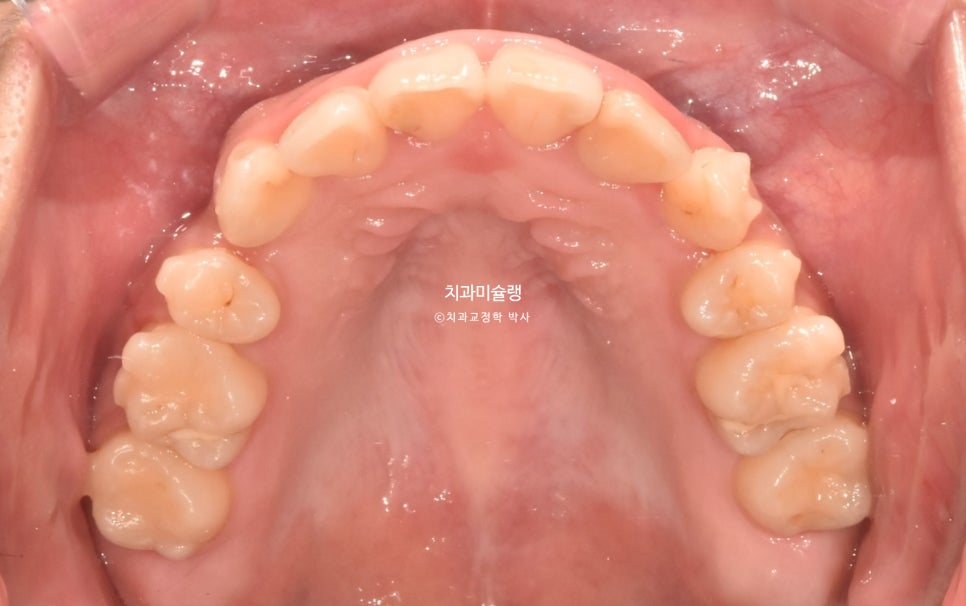

악궁이 소구치 부위가 안으로 쓰러져 찌그러진 모양입니다.

악궁형태나 배열이 이상적입니다.